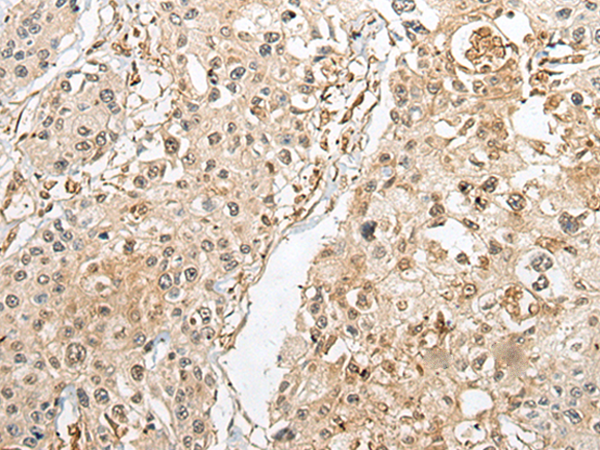

分类: 科研抗体货号: P02445别名: CLI; AAG4; APOJ; CLU1; CLU2; KUB1; SGP2; APO-J; SGP-2; SP-40; TRPM2; TRPM-2; NA1/NA2应用: IHC反应种属: Human, Rat